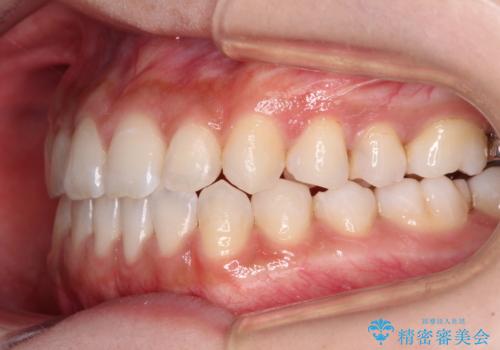

舌突出癖で口元が開いてしまう 舌トレーニングを行ったインビザライン矯正

- 前歯の上下スペースと前歯の隙間を気にして来院された患者様です。

インビザラインにより上下の前歯の隙間を閉じていくこととしました。

上下の隙間に舌が入り込むことが、すきっ歯やオープンバイトの原因であったため、舌の筋肉のトレーニングも並行して行い、後戻りの抑制を図りました。